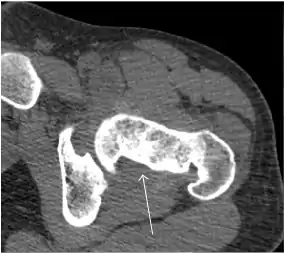

Computed Tomography

Due to radiation concerns, CT has been relegated after MRI in the study of intra-articular causes of hip pain. The only exception where CT is considered superior to MRI is in bone tumors, because of its ability in characterizing matrix calcifications, and in depicting the anatomy of acute traumatic fractures. Typical matrix calcifications include the following: (a) osteoid mineralization, like a dense cloud, (b) chondroid calcification, reproducing a punctate popcorn pattern, or (c) fibrous calcification, ground glass-like appearance. There are also tumors that typically do not show matrix calcification. CT is also used for accurate localization of the nidus in osteoid osteomas and this must be differentiated from Brodie’s abscess or a stress fracture. The current standard treatment of osteoid osteoma is percutaneous radiofrequency ablation and this is usually performed under CT guidance.[1]

Quite often, CT is widely available unlike MRI, especially in the acute setting. CT is performed in this setting when doubt about the existence of a fracture persists following plain radiograph. Modern multidetector computed tomography (MDCT) shows results comparable with MRI for detecting occult fractures.[1]

Due to the submillimeter resolution of MDCT arthrography, many authors consider this technique complementary to MR arthrography. It may even have superior sensitivity in detecting cartilage pathology, but lesser detecting labral tears.[1]